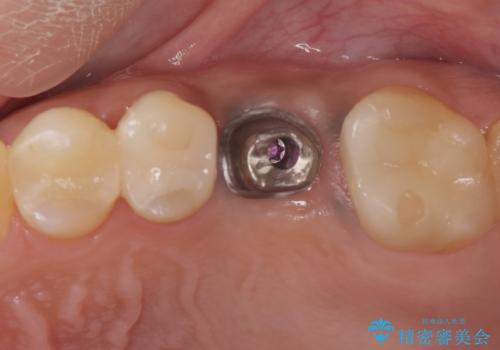

予後の悪い歯を抜歯 インプラントでの治療

- 検査の結果、長くもたせることが困難な歯が確認された患者様です。

抜歯を行い、周囲の骨を増やしつつインプラントを埋入することとなりました。

良い位置に良い方向でインプラントを埋入することができました。